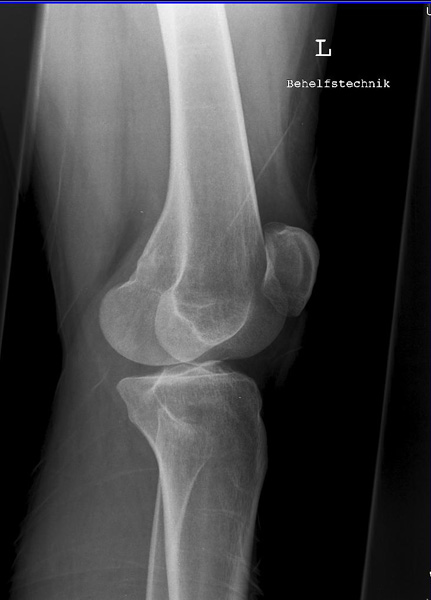

Kniegelenk

Knie a.p.

120_2.jpg

Fehler

Beide Gelenkfacetten des Tibiakopfes stellen sich oval dar, auf der einen Seite höher als auf der anderen; so kommt es im Röntgenbild zur Überschneidung mit den Gelenkkondylen des Femur und unter Umständen auch zu einer Verdeckung der Eminentia intercondylaris.

Abhilfe

Der Zentralstrahl muss bei jeder Knieaufnahme, sei es bei gestrecktem oder gebeugtem Knie, immer senkrecht auf die Längsachse der Tibia treffen.